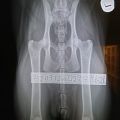

HD x-ray Simba

The time had come for my big boy to examine his hips. The x-ray pictures have been sent to both PawPeds and OFA for reading, mostly because I’m interested in comparing the results.The wait is the worst, I’m so excited!I… Les mer ›